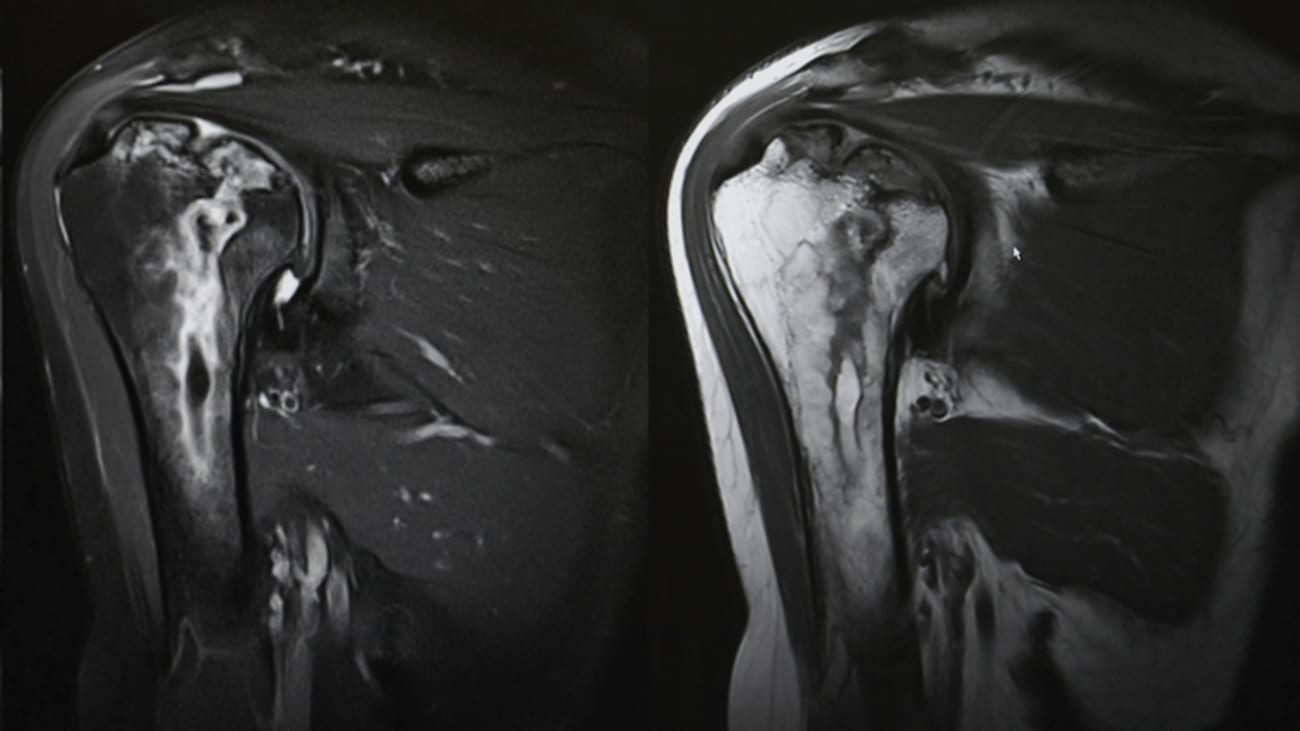

When shoulder pain develops, doctors often order magnetic resonance imaging (MRI), a detailed scan that uses magnets and radio waves to visualize soft tissues. MRIs can detect:

- Tendinopathy: Degeneration or irritation of a tendon

- Partial-thickness tears: Tears affecting part of the tendon

- Full-thickness tears: Complete tears through the tendon

Researchers in Finland examined 602 adults between the ages of 41 and 76. Participants underwent shoulder examinations and high-resolution (3-Tesla) MRIs of both shoulders. They were also asked whether they had experienced shoulder pain or difficulty using their shoulder in the previous week.

The most common issue was partial-thickness tears (62 percent), followed by tendinopathy (25 percent) and full-thickness tears (11 percent). While full-thickness tears were slightly more common in painful shoulders, that difference disappeared after researchers adjusted for age and other factors. Abnormalities increased with age but were equally common in men and women.